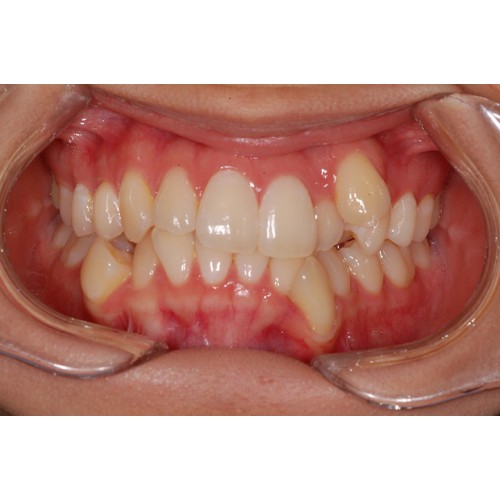

CHUNCHU'S ORTHODONTIC CLINIC# BEFORE_AFTER

춘추치과교정과를 방문해주신 분들의전후 사진을 확인해보세요.